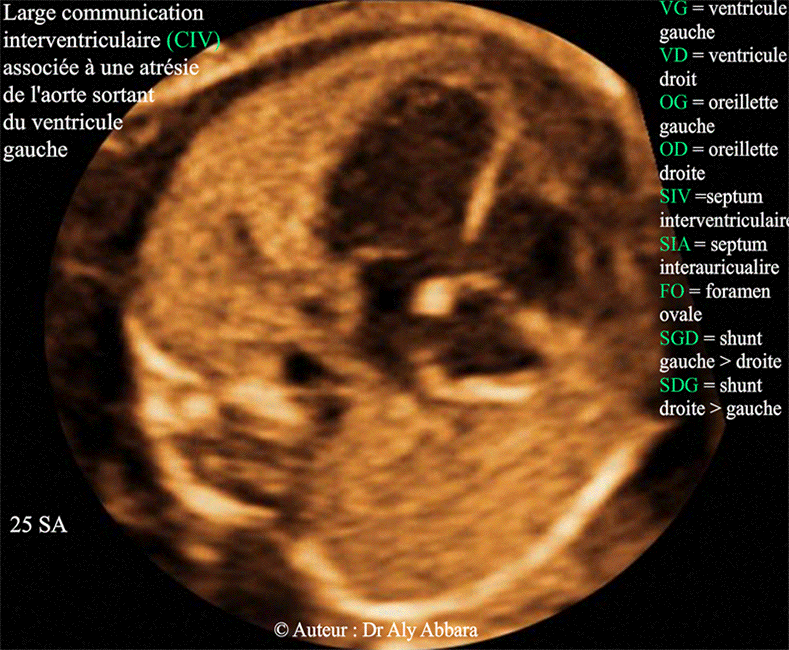

Communication interventriculaire associée à une atrésie de l'aorte ascendante - 25 SA - Echographie

• Coupe échographique de quatre cavités cardiaques montrant la présence d'une large communication inter-ventriculaire (CIV).

Il s'agit d'une communication inter-ventriculaire de type CIV d'admission (située au niveau de " Inlet septum ").

• Cette anomalie de septum interventriculaire (SIV) est associée à une atrésie de la l'aorte ascendante dès sa sortie du ventricule gauche (aucun vaisseau sort du ventricule gauche). Grâce à l'important shunt gauche > droite (SGD) le volume des quatre cavités cardiaques reste équilibré.

L'image montre aussi le foramen ovale (FO) au niveau du septum inter-auriculaire (SIA) avec le shunt droite > gauche (SDG) physiologique dans la vie in-utero.

En dehors des ces anomalies cardiaques, pas d'anomalie associée au niveau d'autre organe, avec caryotype fœtal normal et absence de micro-anomalie au niveau du chromosome 22. Biométrie en rapport avec le terme (25 SA).